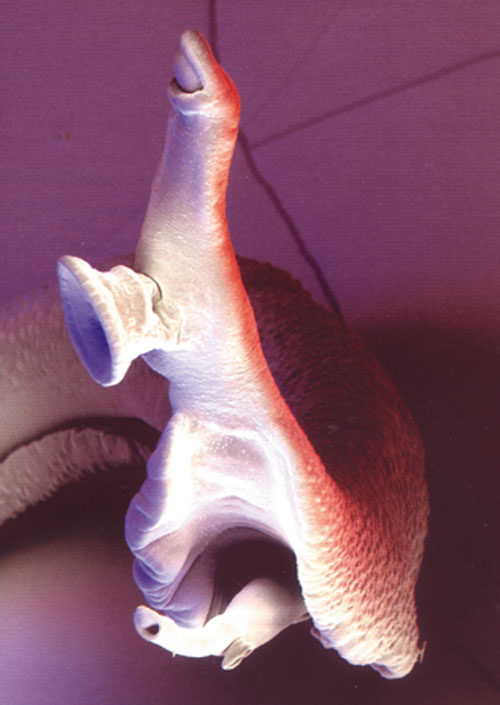

Unlike most parasitic worms, which inhabit the intestines, lymphatic filariae live in the lymphatic vessels and nodes. For reasons not completely understood by scientists, the presence of these worms in the lymph system can lead to severe inflammation called elephantiasis, which often affects the legs, arms, genitals and breasts [see photo]. Unfortunately for men, the worms have a propensity for the male genitalia. The worms get inside a person's body when a mosquito carrying their larvae sinks its proboscis into a victim's skin. The larvae travel through the skin and into the lymph vessels where they mature into adults measuring as long as four inches (100 millimeters). According to WHO, the infection usually begins in childhood but often takes years to cause elephantiasis.

Some 120 million people, mostly in the warm, humid climes of south Asia, Africa and the Americas, are infected with these tiny worms, and more than 40 million are disfigured by the infection, according to WHO.